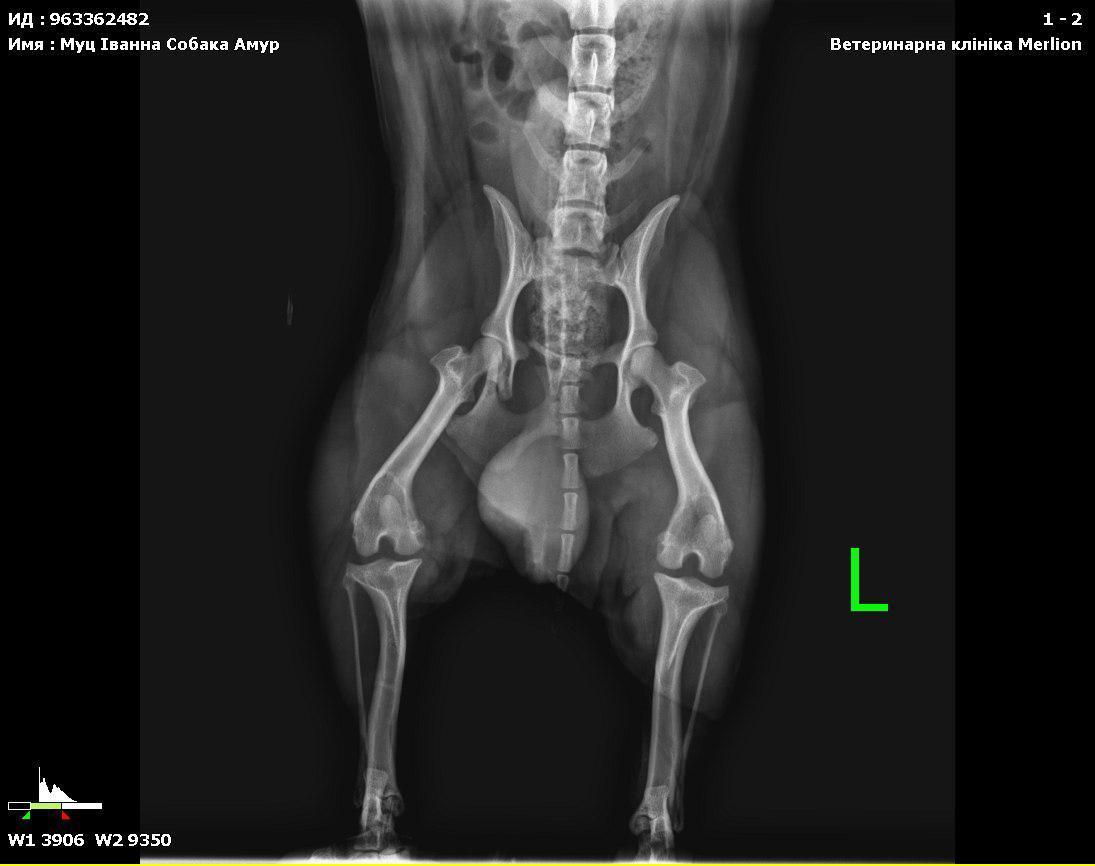

In der Klinik stellte sich heraus, dass Gucio etwa 3 Jahre alt ist und eine gebrochene Beckenregion hat. Wahrscheinlich wurde er von einem Auto angefahren. Deshalb konnte er sich nicht bewegen und lag an einer stark befahrenen Straße — ohne jede Chance, wenn niemand angehalten hätte.

Er erhielt erste tierärztliche Hilfe — Untersuchung, Impfung, Entwurmung. Sein Zustand wurde als schwer eingestuft: starke Unterkühlung, Erschöpfung und eine Verletzung, die eine langfristige Behandlung und Rehabilitation erfordert.